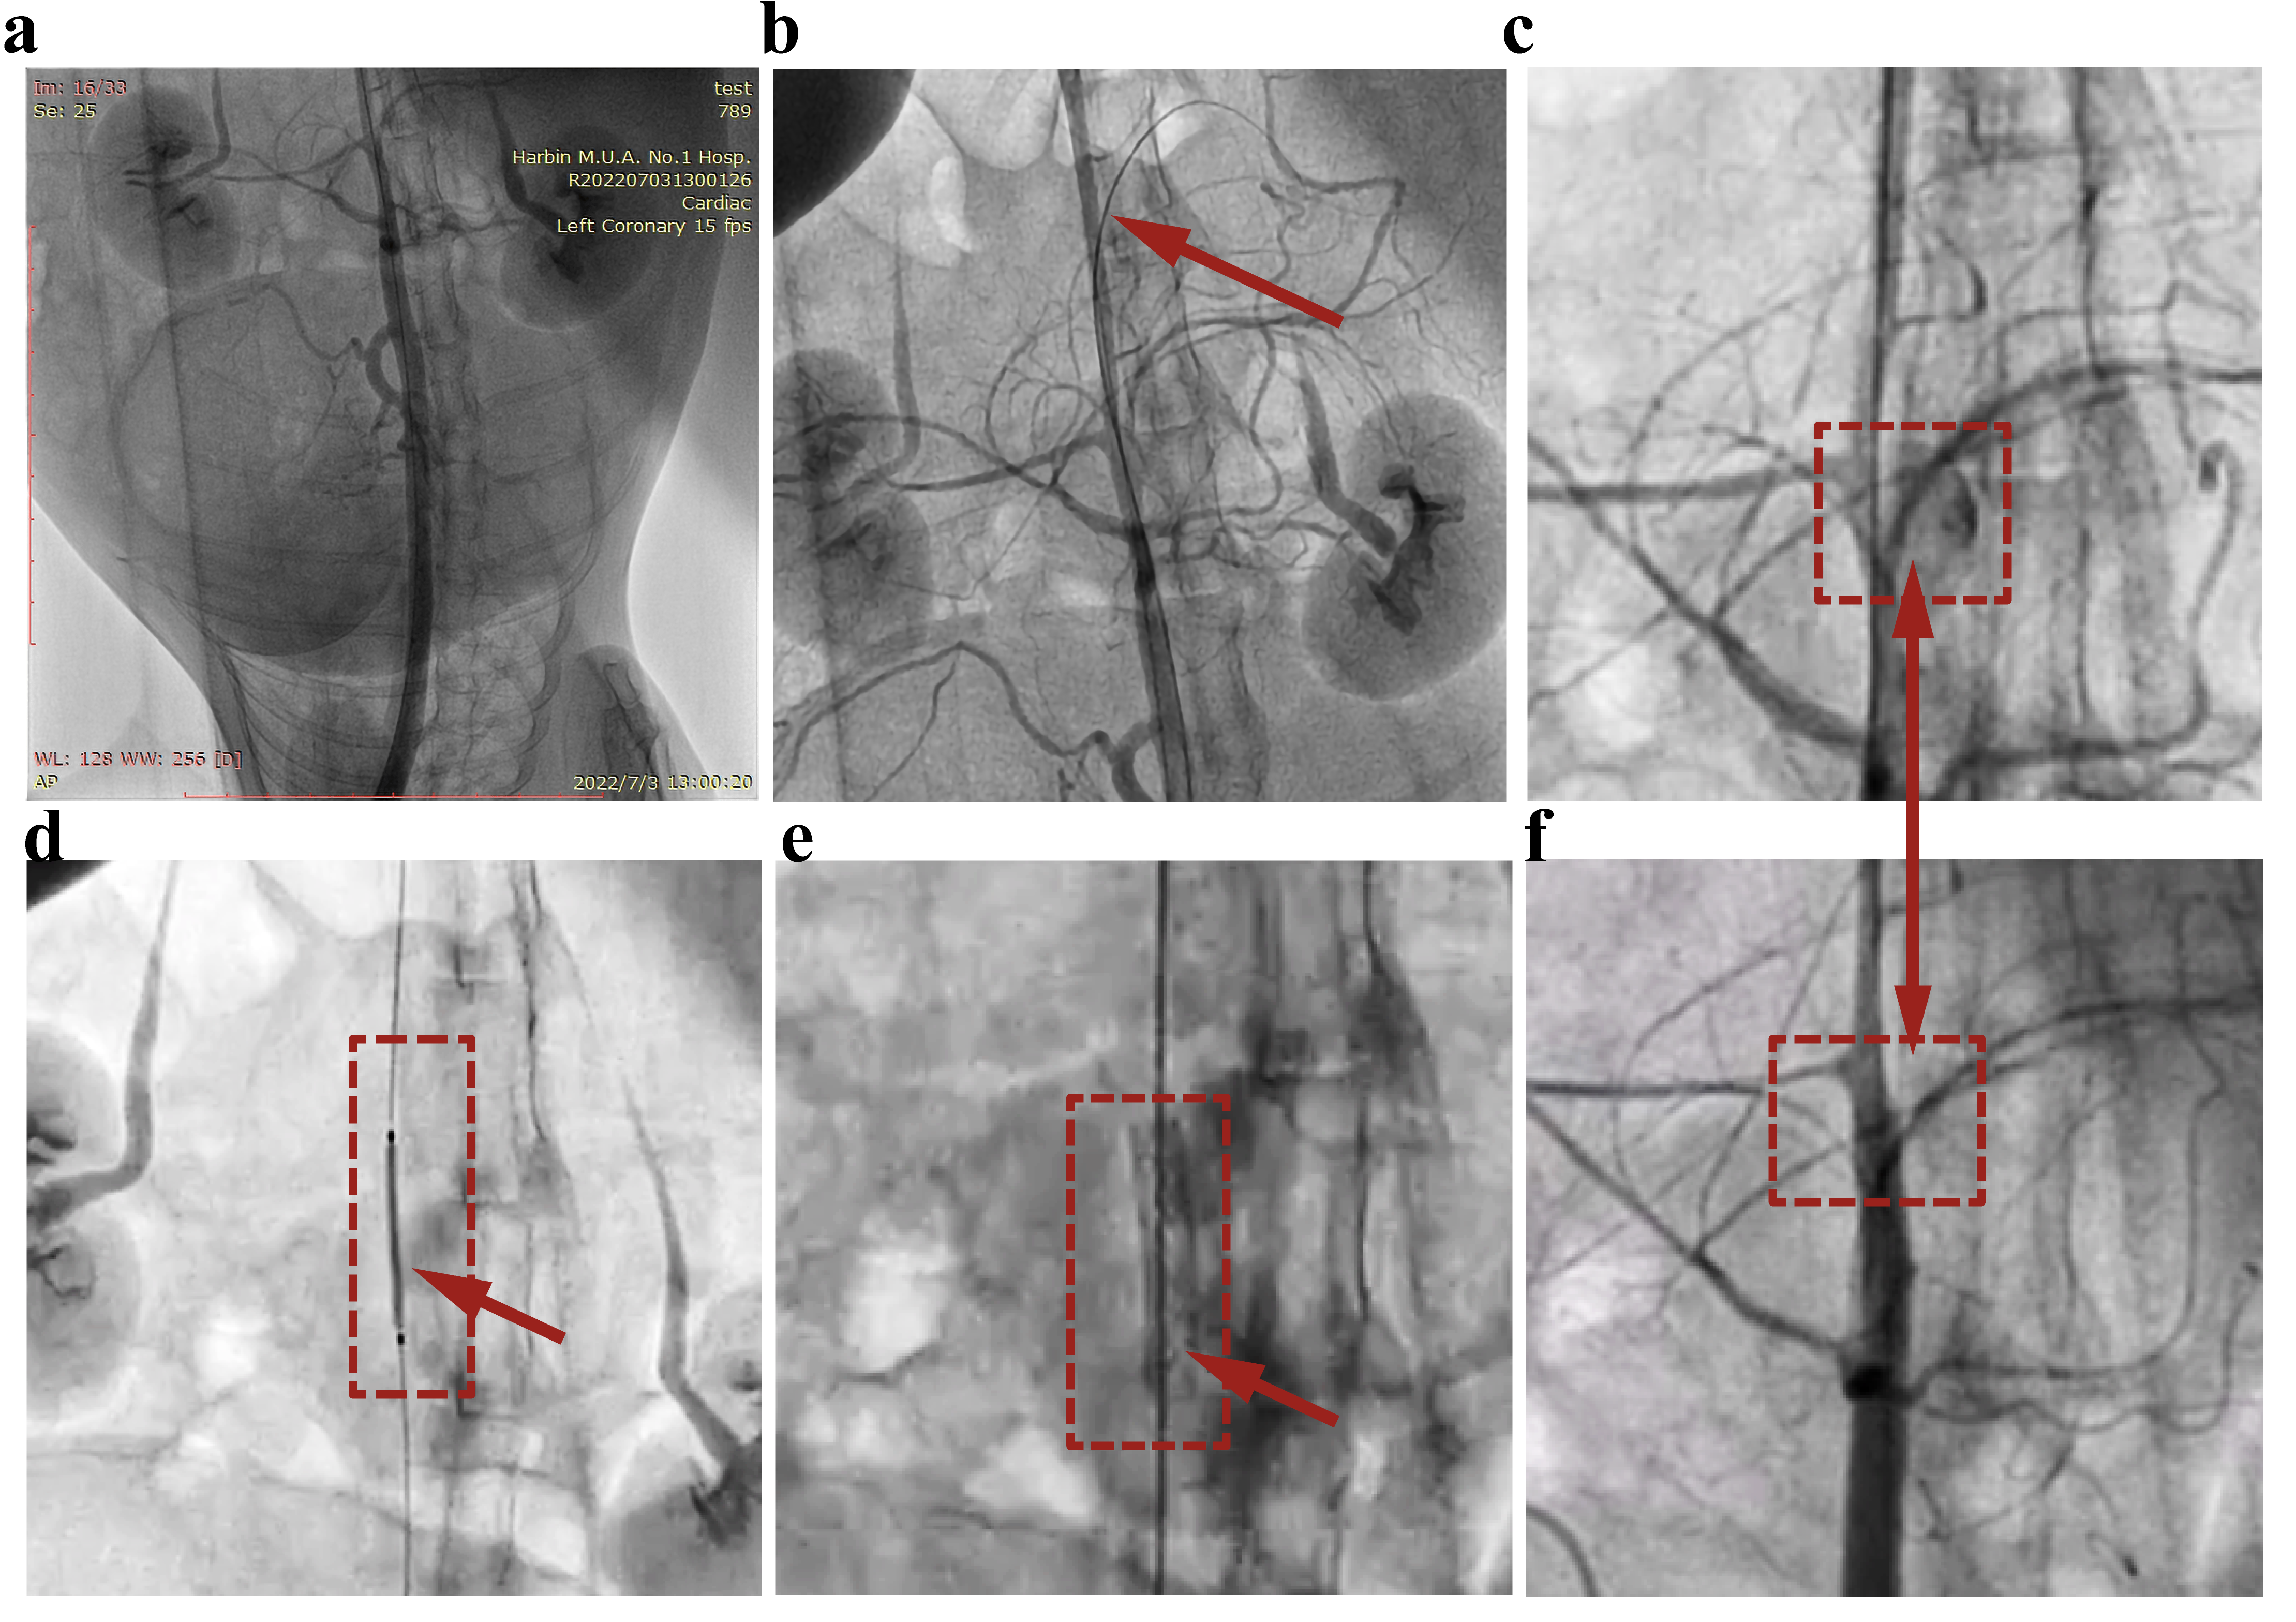

3.3. Covered Stent Deployment in the Rabbit Abdominal Aorta